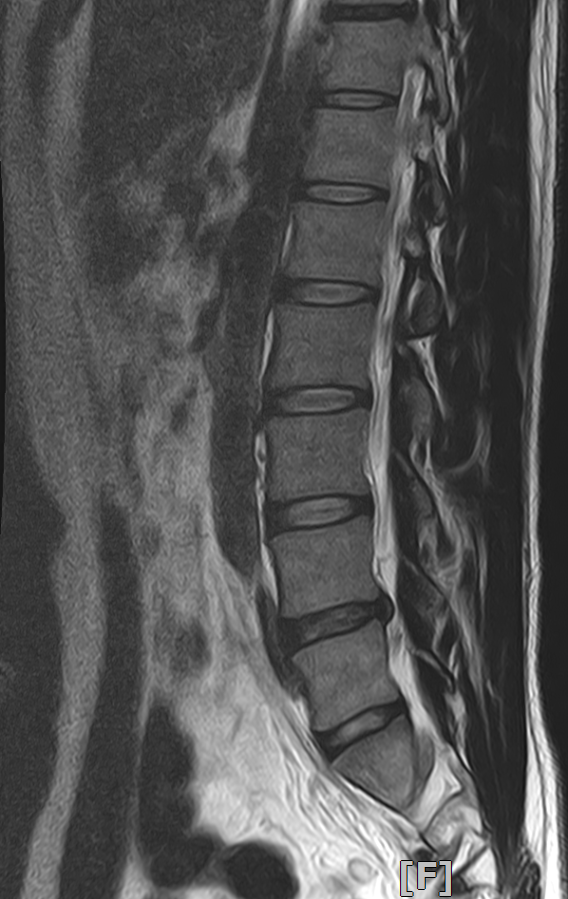

두가지 증상 때문에 요추와 골반 MRI 를 촬영하게 되었습니다.

저는 각기 다른 질환 (고관절충돌증후군과 척추관협착증) 을 의심하였는데 병원에서는 모두 허리디스크 퇴행으로 인한 것이라고만 설명해서 실제로 다른 가능성은 없는것인지 궁금하여 질문 남깁니다.

아래 영상 첨부하였지만.. 이정도 상태로 아래와 같은 두가지 증상이 생기는 것이 상식적인 이야기인지 궁금합니다. (골반 영상은 무엇을 첨부해야할지 몰라 첨부하지 않았지만 영상상으론 아무 문제 없다고 들었습니다.)

평상시에 1시간씩 빠른 속도로 걷는 것을 즐겨하고 산책도 좋아하는 편인데, 유독 느린 템포로 가다 서다 반복하는 경우에 시간이 얼마 지나지 않아 허리가 끊어질것 같은 느낌이 듭니다. 심하면 집을 나선지 30분도 안되어 통증이 발생하여 점점 심해집니다. 눕거나 쪼그려 앉으면 바로 증상이 바로 완화되고, 앉아서 등을 기대면 괜찮아지기도 합니다. (디스크로 인한 문제보다는 척추관협착증과 관련있지 않나 의심)

두 가지 증상은 허리 디스크 뿐 아니라 다른 원인일 수도 있습니다. 고관절 충돌 증후군이 관련될 수 있고 요추나 골반의 비정상적인 움직임이 통증을 유발할 수 있습니다. 또 척추관 혐착증도 의심되므로 mri결과를 통해 정확한 원인을 파악하는 것이 중요합니다

우선 mri와 질문하신 내용들을 종합해봤을때 증상으로는 충분히 고관절충돌증후군 또는 고관절활액막염이 의심이 가는 증상이고, 척추관협착증에서 나타나는 증상이기도 합니다 (빠른 시일내에 호전을 보이셨기에 이 부분은 확인 해보셔야 할것 같습니다).

다만 mri상 허리 척추 뼈와 뼈 사이의 공간은 협착증이 심해 보이진 않고 다만 퇴행성의 모습이 보이기도 합니다.

현재 증상들은 퇴행성 디스크에 의한 증상들과도 비슷한 증상들이 많기에 감별 진단이 필요한 부분입니다.